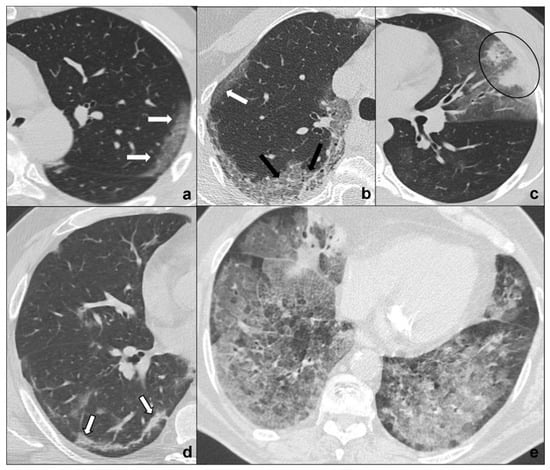

- tumors are generally focal entities and appear as ground-glass opacities (atypical adenomatous hyperplasia likely being ≤5 mm, adenocarcinoma in situ generally being bigger, even measuring ≤3 cm), or ground-glass opacity surrounding a nodule (≤5 mm in minimally invasive adenocarcinoma and >5 mm in lepidic predominant adenocarcinoma);

- even if tumors are multicentric, such as invasive mucinous adenocarcinoma, they tend to grow even after antibiotic or anti-inflammatory treatment;

- additional findings such as cysts (cystadenocarcinoma);

- cleavage invasion;

- lymphangitic carcinomatosis (Figure 3b);

- mediastinal lymphadenopathies (Figure 4e) and pleural effusions.